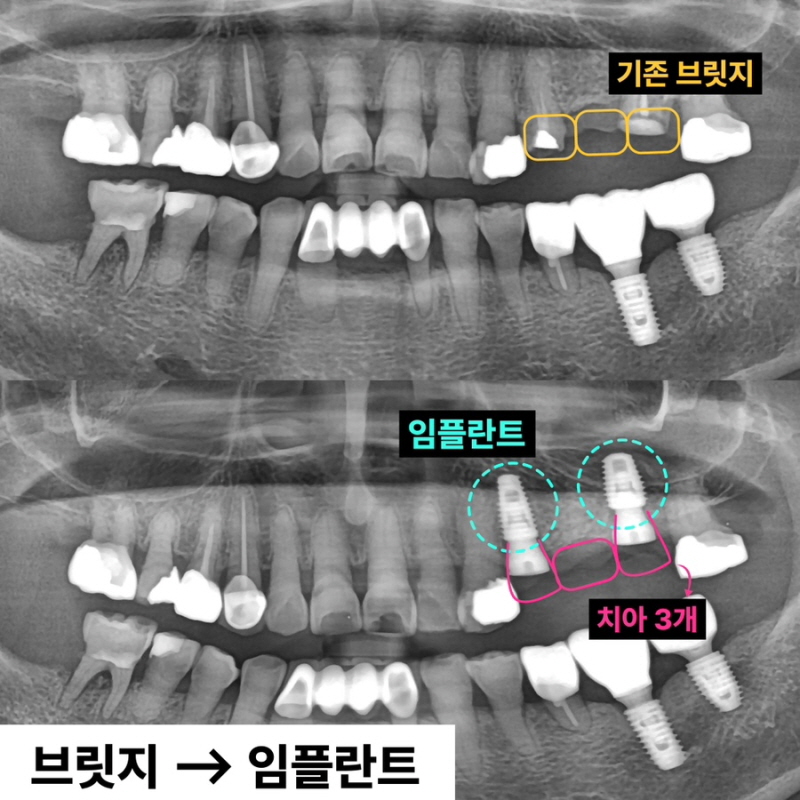

이미 신경치료된 치아 뿌리 끝에 염증이 잡혀있고 브릿지 아래로 2차충치가 크게 생겨서 임플란트로 치료 계획을 정했습니다. 임플란트 2개를 심고 치아 머리(크라운) 3개를 만듭니다. 여러 개의 임플란트를 심을 때 꼭 개수대로 임플란트를 심을 필요는 없습니다. 과거에는 발치, 상악동 수술, 임플란트를 전부 기다리며 나눠서 진행했는데 시간이 너무 오래 걸립니다. 저는 최대한 치아가 없는 기간을 단축시키기 위해서 치아를 뽑고(발치) 동시에 임플란트를 심으며 뼈가 없는 경우 상악동 수술을 동시에 진행합니다.

발치, 상악동 거상, 임플란트 식립 모두 이상적인 모습입니다. 과거 임플란트가 없던 시절에는 브릿지 치료가 일반적이었습니다. 하지만 현재는 치아가 없을 때 양 옆의 치아를 갈아서 씌우는 치료는 임플란트 등장으로 없어지고 있습니다. 또한 오래된 브릿지가 흔들리거나 잇몸에 염증이 생긴다면 임플란트로 교체가 필요할 수 있습니다.